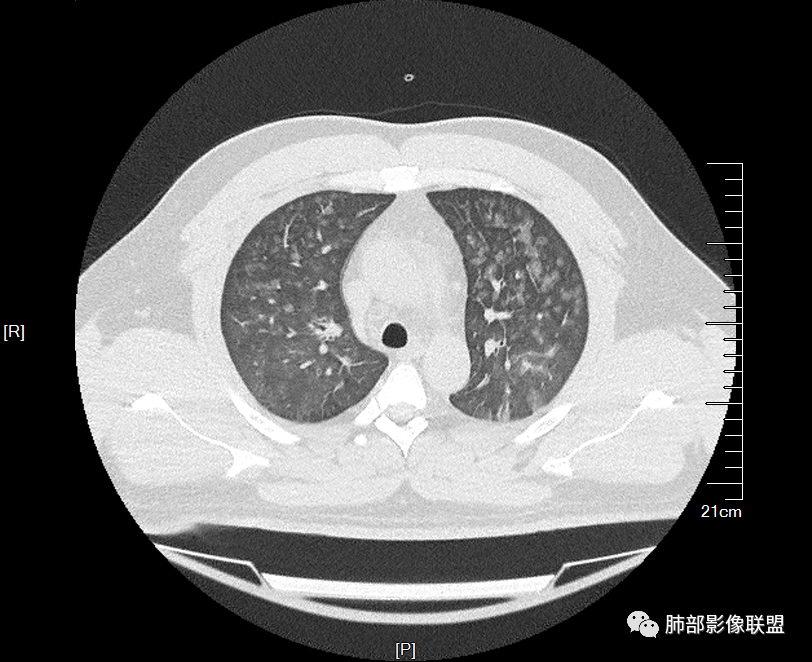

双肺多发弥漫性磨玻璃结节影,大小不一,形态不规则,部分融合,支气管未见明显扩张,部分血管束略增粗,叶裂胸膜增厚,临床有痛风,左足痛6天,考虑:1:痛风结节(一般实性结节,很少磨玻璃结节影)2:血管炎?3:病毒性肺炎(水痘-疱疹肺炎?)

双肺多发腺泡结节及磨玻璃,小叶间隔增厚(大网格状),腺泡结节内及磨玻璃内可见细网格影(小叶内间隔增厚),影像表现符合肺泡出血改变,血肌酐升高,考虑肺肾综合征。鉴别肺水肿。

年轻男性,痛风史,高血压史,肌酐高,左足痛6天入院。胸CT:双肺多发弥漫性磨玻璃结节影,大小不一,部分融合,上中下肺都有,中内带多,胸膜下少。部分血管束略增粗,小叶内间隔、小叶间隔增厚,下肺明显,左室大。叶裂胸膜增厚。临床有痛风,左足痛6天,考虑:心衰、间质性肺水肿?弥漫性肺泡出血?鉴别:MPA,肺肾综合征,痛风结节等。

多发GGO结节,边界清,以全小叶、小叶中心为主:

小叶间隔增厚,无明显重力趋势

中轴间质稍增厚

中轴间质增厚,小叶间隔增厚,小叶内间质增厚,部分重力作用,双侧对称,胸水,按理淋巴道回流受阻有

问题是腺泡结节如何解释?

一般吸入性病变,肺泡腔充填性病变